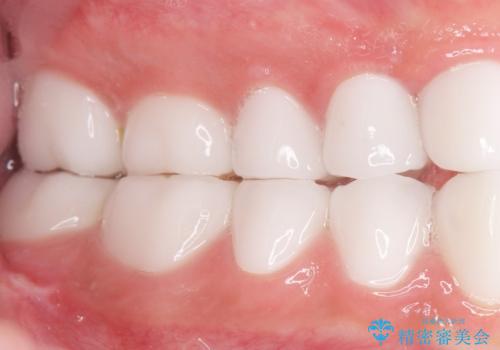

憧れのヴィジュアル系バンドマンのような白い歯になり、喜んで下さいました。

不適なレジン充填によるデコボコがなくなったことで歯磨きしやすくなり、また気にされていた咬み合わせも良くなり、ご満足頂けました。

クラウンの種類:オールセラミッククラウン スタンダード

シェード:NW0